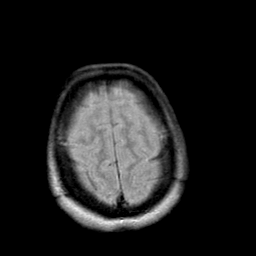

Creutzfeld-Jakob disease: proton density-weighted MR -- Slice #20

[Home][Help][Clinical] Slice 20